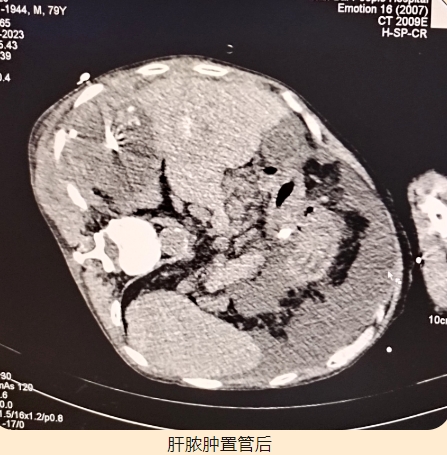

80歲的楊大爺,2016年1月被診斷為“原發(fā)性肝癌”,外院先后共行4次介入治療術(shù),2018年11月和2022年4月期間兩次復(fù)發(fā),再次行介入治療,直至今年因消化道出血并肝性腦病到我院ICU住院治療,盡管治療后病情有所緩解,但身體恢復(fù)很差,反復(fù)腰腹痛,乏力,胃口差,精神疲倦,最后轉(zhuǎn)入腫瘤介入科進(jìn)行進(jìn)一步治療。復(fù)發(fā)肝癌,發(fā)展速度迅猛,生命岌岌可危,加上楊大爺年紀(jì)較大,難以經(jīng)受病情的反復(fù)折磨,家屬更是一籌莫展。急病人所急,想病人所想,我院集中力量再次請(qǐng)到廣東省人民醫(yī)院腫瘤介入科許榮德教授會(huì)診,經(jīng)過(guò)一番縝密的病情討論,決定施行CT引導(dǎo)下肝癌微波消融術(shù)+肝囊腫穿刺術(shù)。在許榮德教授的帶領(lǐng)下,我院腫瘤介入科團(tuán)隊(duì)順利完成我院首例肝癌微波消融術(shù)。肝囊腫穿刺抽出膿液,予以留置引流管。術(shù)后楊大爺逐步恢復(fù),腰腹痛明顯減輕,胃口、精神顯著改善,他和家屬的臉上都露出了久違的笑容,還夸贊醫(yī)護(hù)人員技術(shù)精湛,品德高尚!